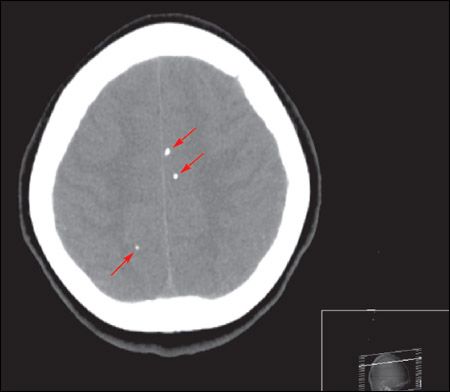

A cranial CT scan showed calcifications (arrows) scattered throughout the brain parenchyma with hydrocephalus. Intravenous ceftriaxone and metronidazole were started; phenytoin was added after seizures developed. Results from blood cultures were negative. The patient underwent a ventriculoperitoneal shunt. Results of cerebrospinal fluid analysis and culture, Cytomegalovirus serology, Toxoplasma serology, and tuberculosis polymerase chain reaction were all negative. Serology for Taenia solium was reactive. Postoperatively, albendazole (800 mg/d) and dexamethasone were started.

Neuroimaging may show a nonenhancing hypodense lesion, variable degrees of edema, calcifications, or hydrocephalus. Conditions that can present with similar features include toxoplasmosis, schistosomiasis, tuberculosis, cytomegalovirus infection, abscess, primary brain and metastatic cancers, trichinosis, and sarcoidosis. Finding a scolex as a mural nodule within the cyst is pathognomonic for neurocysticercosis. The appearance on CT or MRI scans is frequently nonspecific and may be difficult to differentiate from other brain lesions. A definitive diagnosis can be made using proposed diagnostic criteria based on clinical presentation, imaging, serology, and epidemiological data.3